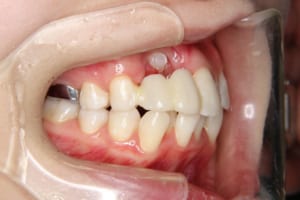

治療後

その他/備考 上顎右側中切歯および側切歯が、埋伏していた犬歯によって歯根吸収していました。

牽引に半年かかりました。

顎間ゴムも頑張ってくれたが期間がかかりました。

いずれ牽引した犬歯の再度の補綴処置を予定しています。